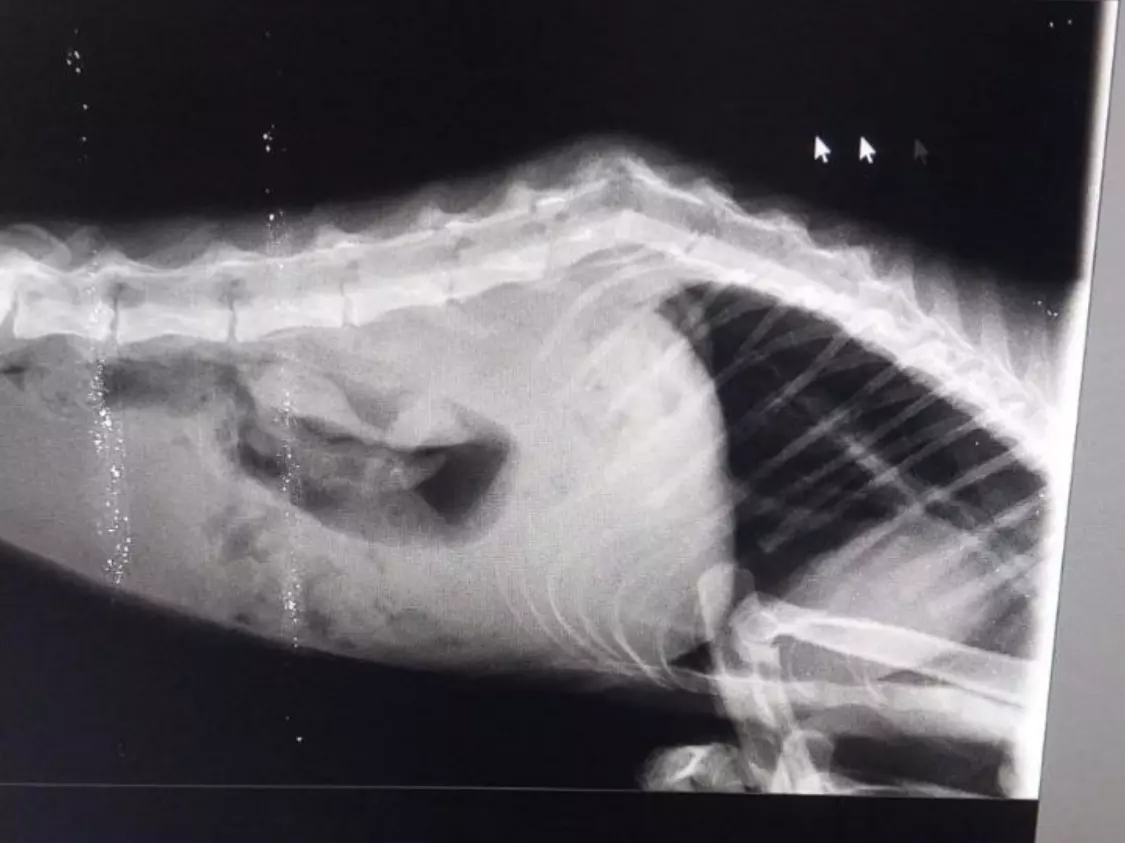

После небольшой адаптации в клинике кошка начала потихоньку есть. Однако на лапки Венера так и не вставала. У сотрудников приюта появилось подозрение, что у нее перелом позвоночника. Чтобы сделать рентген, питомца нужно было отвезти в Белую Калитву.

После рентгена врач подтвердил диагноз - у Венеры перелом позвоночника. Кошечке назначили терапию и рекомендовали сделать МРТ.